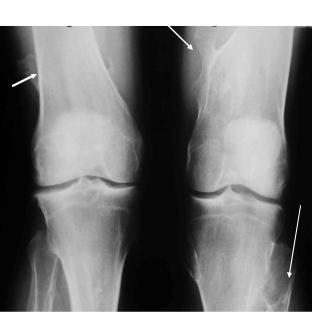

В случае затяжного или хронического течения могут выявляться: околосуставной остеопороз (непостоянный признак) поражѐнных суставо в изменения в области поражѐнных энтезисов (эрозии, сопровождающиеся субхондральным склерозом и костной пролиферацией (рис. 6-4), периостит в случае дактилита), сакроилеит (обычно односторонний), спондилит (очень редко). При хроническом течении возможно сужение суставной щели и развитие костных эрозивных изменений (почти исключительно в мелких суставах стоп). Отличительной особенностью рентгенологических изменений при спондилоартритах вообще и при РеА в частности является наличие в области зон воспаления и деструкции остеосклероза (а не остеопороза, как при РА) и костной пролиферации (в области краевых эрозий, воспалѐнных энтезисов) и периостита.

Рис. 6- 4.Многочисленные грубые периоститы, как исход длительно существующих энтезитов на фоне реактивного артрита.